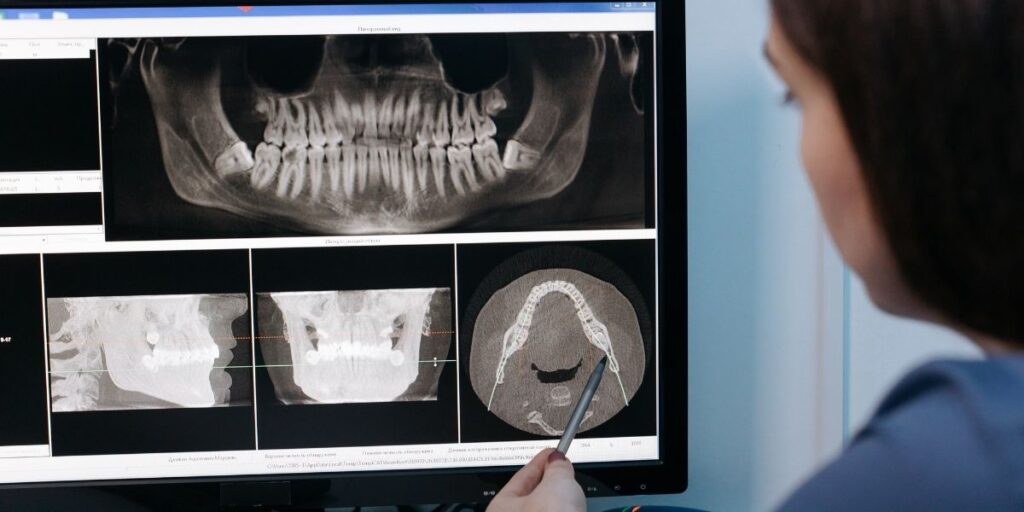

Since it was clear from the get-go that we will be developing handcrafted solutions for each eligible dental implant case, we started with the intra oral scans of the patient. These scans were converted into the CBCT format, a 3D digital file of the scan which also shows the hollow location (the socket) that needs to be filled for the dental implant to be placed. Hence, the design of the implant was based on each CBCT.